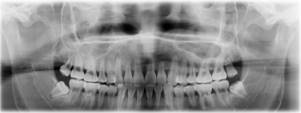

CT/放射影像简介

计算机断层扫描(CT)技术利用X射线的穿透特性,根据不同组织对X射线吸收程度的差异,导致探测端接收到的射线强度发生变化。探测器捕捉这些变化,并将其转化为电信号,随后通过模数转换器输入计算机。计算机运用Radon变换和反投影算法等复杂的数学处理方法,重建出样品某一层面的二维图像。如果对多个层面进行连续扫描,可以进一步生成三维图像,从而全方位、多层次地展示样品内部的精细结构。这项技术为医学治疗、器件检测、考古研究、工业检测和安全检查等多个领域提供了重要的分析依据。

CT/放射影像原理

医用CT(影像识别)中,当一束射线通过被测对象的一个断层时,人体各种组织(包括正常和异常组织)对X线的吸收不等。

CT将人体某一选定层面分成许多立方体小块,称为体素。照射时可用探测器的每一个像素进行测量。像素之间排列成线阵。探测器将射线强度转换成电信号,经过数字化后由计算机处理。

当X线球管从一方向发出X线束穿过选定层面时,沿该方向排列的各体素均在一定程度上吸收一部分X线,对面探测器获得所有体素衰减量总和。接着X线球管转动一定角度后重复上述过程,则在其对面的探测器可测得沿第2次照射方向所有体素X线衰减值的总和。经过对选定层面反复多次不同方向的扫描,可获得若干方程,程中X线衰减总量已知,而形成该总量的各体素X线衰减值未知。可由计算机联立方程并求解每一体素的X线衰减值,再经数/模转换,使各体素不同的衰减值形成相应各像素的不同密度或灰度值,最终获得该层面不同密度组织的黑白像素矩阵。